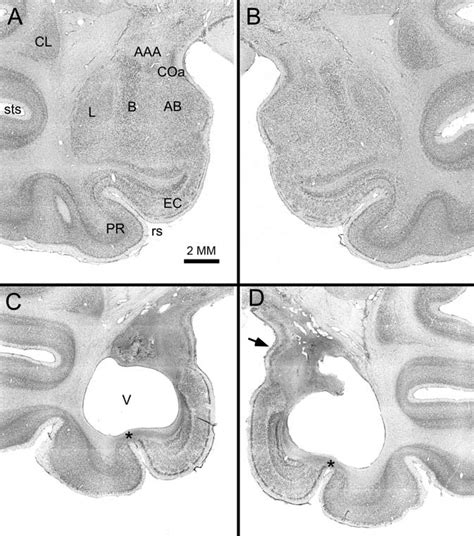

- Photomicrographs Of Coronal Sections Showing A Typical Bilateral ...

- Photomicrographs Of The Typical Amygdala Lesion Produced By ...